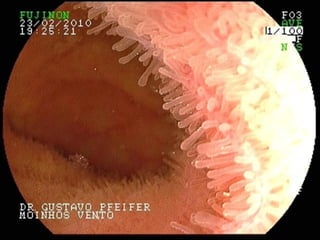

Estrutura:

• válvulas

• vilosidades

• microvilosidades (bordas em escôva)

ABSORÇÃO

É de difícil digestão, por isso pode estimular reações do sistema imune

que poderão desencadear vários sintomas no organismo.

O Glúten agride e danifica as vilosidades do intestino delgado e

prejudica a absorção dos alimentos.